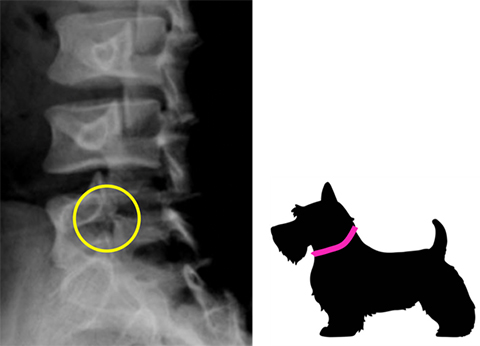

1) 腰椎分離症

過度な腰の反りや捻りがストレスとなり生じる背骨(腰椎)の疲労骨折。腰を反りすぎる動作、捻る動作(回旋)に注意が必要です。X線で骨折線がはっきりする時期には、すでに手遅れ(進行期、終末期)になっていることがあるため、早期診断・早期治療が重要です。2週間以上腰痛が続く場合は、医療機関の受診をおすすめします。

単純X線:スコッチテリアサイン(首輪)